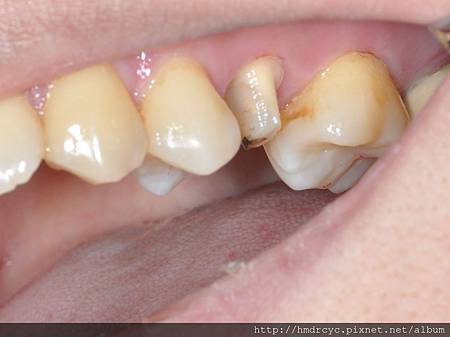

在靠進上顎處缺損嚴重

裂痕延伸至牙肉下

須考慮鑄造鑄心